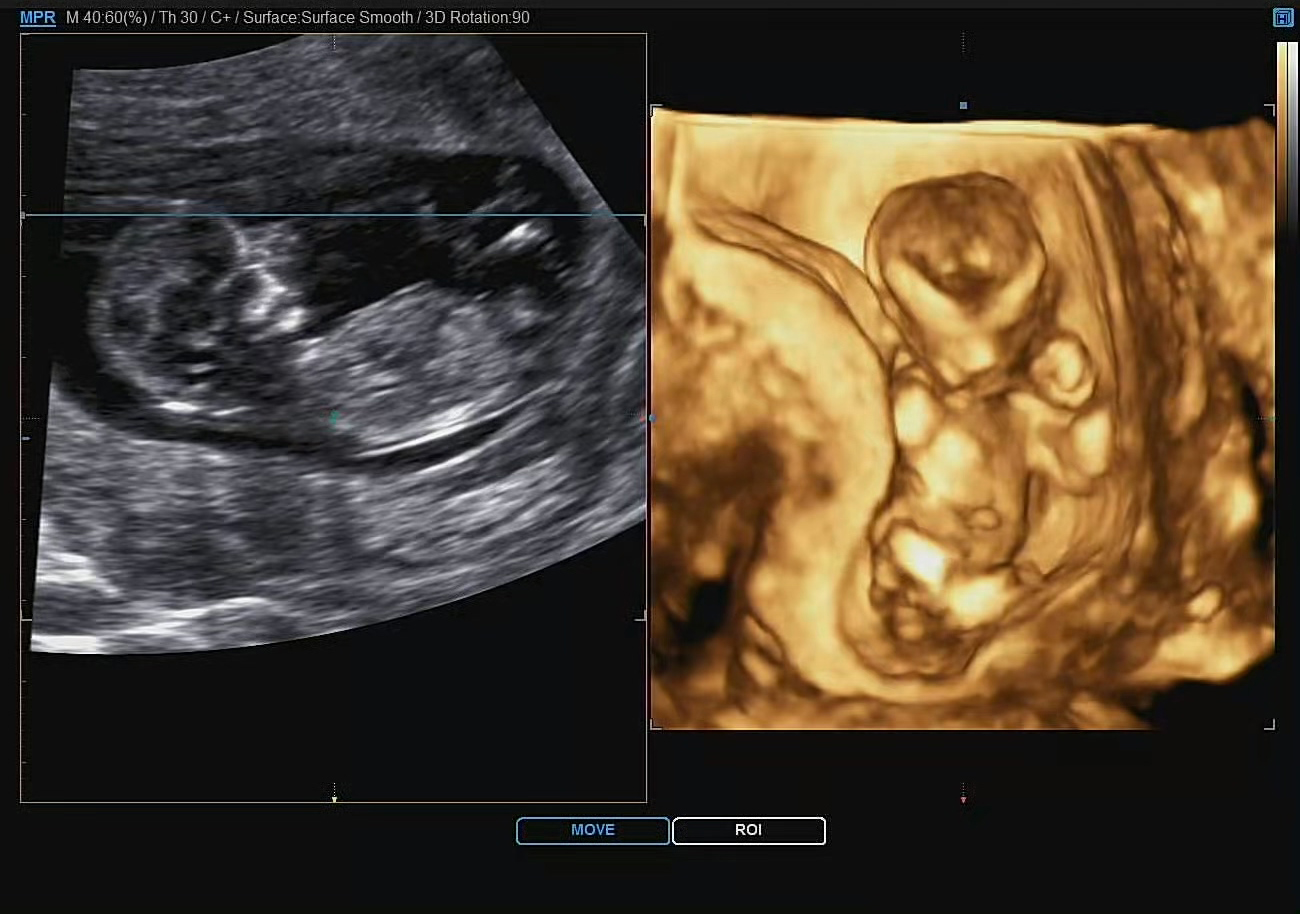

이번 초음파 검사에서는 3D로 구현되는 초음파도 중간중간 있었다. 우리 까꿍이는 숫기가 없는지 두 손으로 얼굴을 자꾸만 가려서 제대로 볼 수가 없었다ㅎㅎ

뚜렷한 이목구비로 확인할 수 없지만, 이렇게나마 까꿍이를 만나는 것은 늘 기다려지는 변함이 없다.